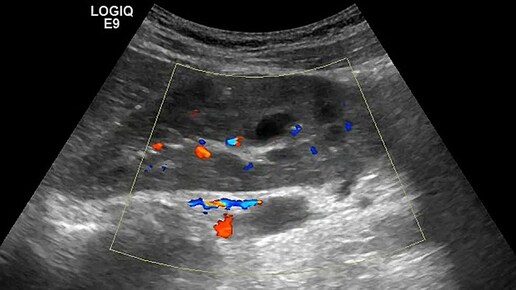

Ультразвуковые находки от врача УЗД Зорина Я.П.